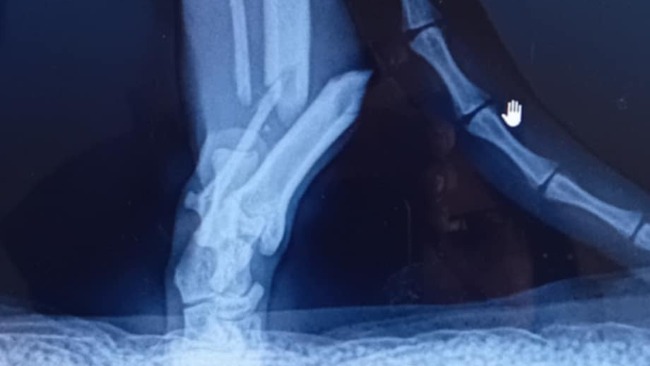

Czesc nazywam sie Szymon postanowilem zalozyc zbiorke na naszego kotka Pedra . W lipcu przyblakal sie obcy kotek i krecil wokol domu okolo tygodnia , zauwazylismy ze kotek jest wychudzony wiec postanowilismy go zaadoptowac i o niego zadbac . Niestety pedro mial ostatnio wypadek i proces leczenia kota jest kosztowny , Bardzo prosze o wplacanie choćby 5 zlotych na pedra bardzo nam to pomoze , Dziekuje <3